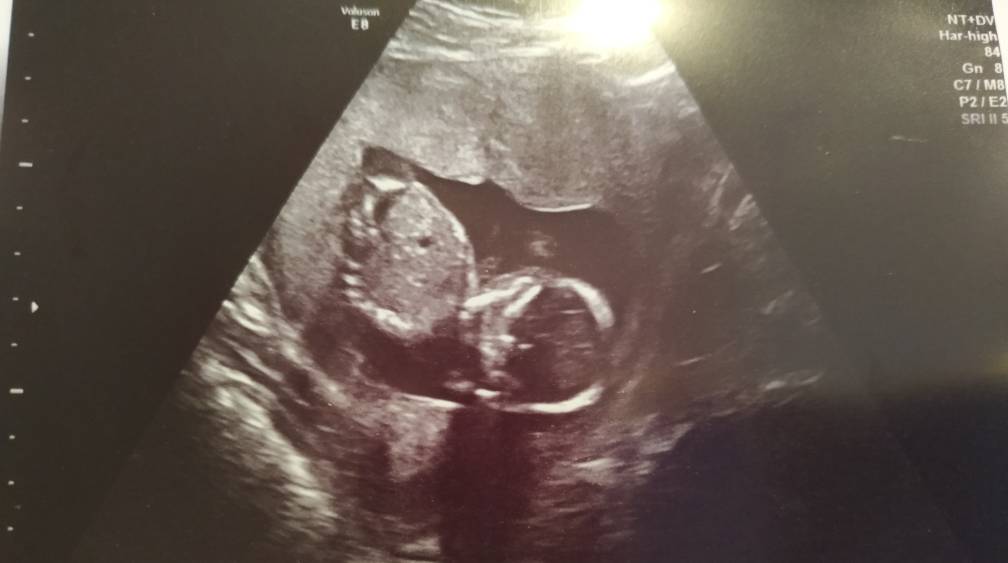

A maluszek cudny [emoji7]

Ależ ona jest przepiękna [emoji173][emoji7]

Ale cudny maly ludzik :) sliczne zdjecie ciesz sie bo za chwile jedyne co zobaczysz to kosc udowa haha :)